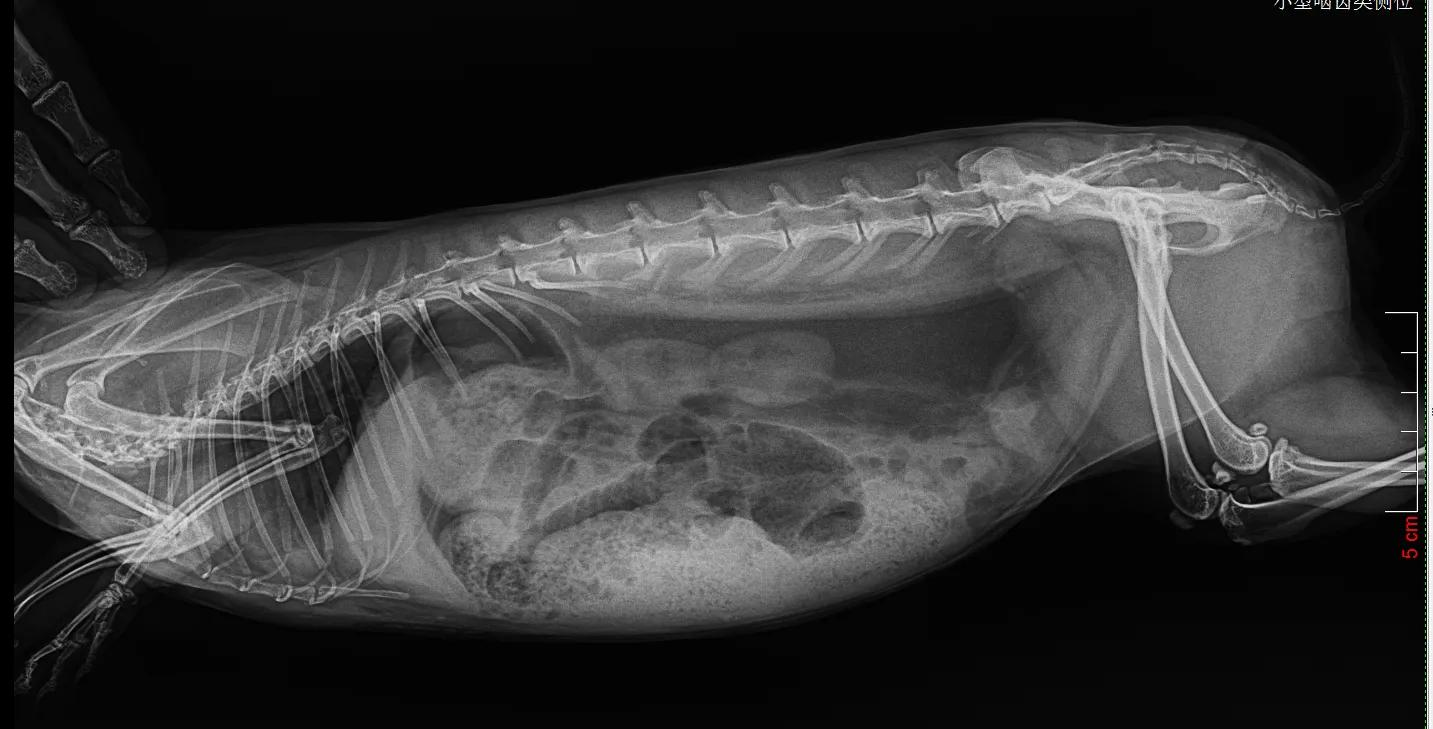

没有犹豫,立刻带它到当地动物诊所拍片,

医生看出来是胀气

表示对治疗兔子并不在行,教我怎么按摩它的肚子。我就坐在诊所帮“汤圆”按摩腹部,那是第一次“汤圆”在我身上趴那么久,它平时太凶悍了,连抓都很难抓到,从来没有一次在我怀里安稳呆过5秒钟。半小时后我要求再次拍片,显示气体有所移动。